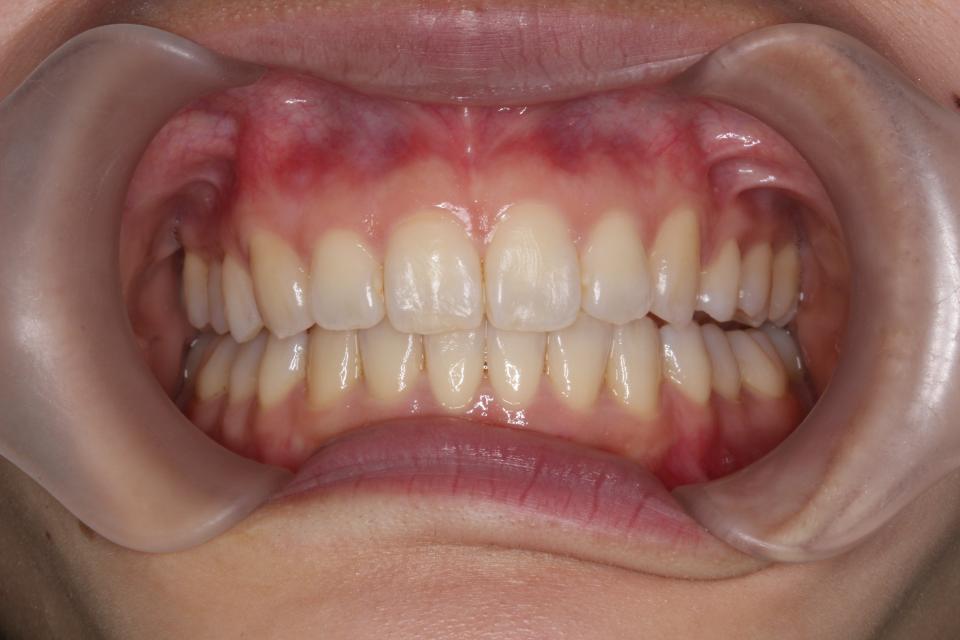

上顎前突(出っ歯)のマウスピース矯正治療例(抜歯あり)

矯正治療後

左上4番目の歯を抜歯して、マウスピース型の矯正治療装置を使用し、歯のやすり掛け(IPR)を行いました。

現在はマウスピース型のリテーナーで後戻りの防止をして定期的にチェックをしています。

| 矯正治療期間 | 2年5か月 |

| 抜歯の有無 | 左上4番抜歯 |